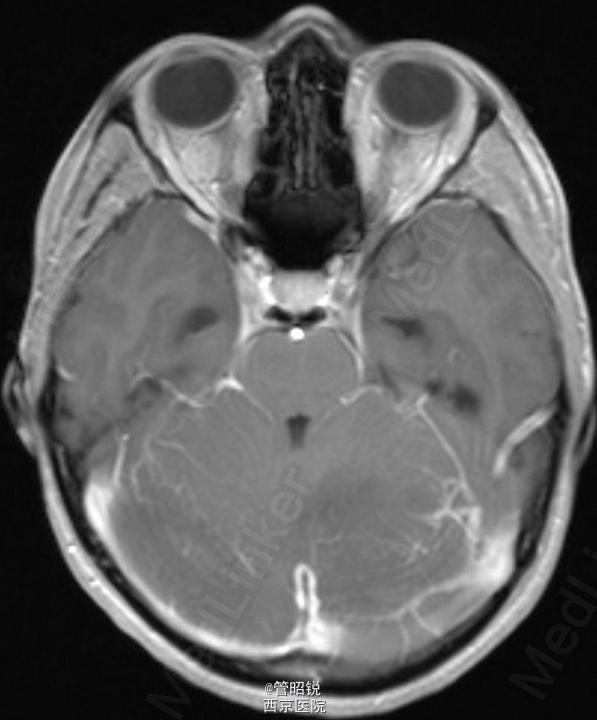

患者,男,29岁,头痛、颈痛2周 入院时CT正常,24小时后 T2WI (B) 和 T2W-FLAIR (C)显示高信号增强,脑水肿,沟回消失。CE-T1WI (D)显示脑膜线样增强。随后12小时的非增强CT显示小脑水肿压迫脑干,由于阻塞性脑积水使颞角膨大,需要紧急行颅后窝颅骨切除减压术。(影像资料比较典型。和大家分享下 AJNR-case of the week)

诊断:急性小脑炎 治疗上应早期应用激素治疗,水肿严重时应手术行颅骨减压。

急性小脑炎是以小脑功能损害为主的炎性综合症。发病前期一般有感染病史,多见于儿童。临床表现多样,主要有躯干和肢体的共济失调,发热,眼球运动异常,言语不清,头痛,恶心、呕吐和意识水平的下降。临床诊断主要依据其典型的影像学检查,临床表现和脑脊液检查结果。